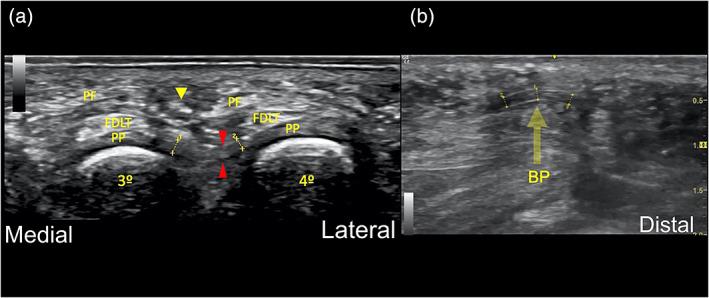

MATERIALS, METHODS, AND RESULTS: The DTML was visualized in 10 fresh frozen donated body to science-feet (eight male and two females, five left and five right) using an US device (GE Logic R7; 13 MHz linear probe, Madrid, Spain). Consecutively, minimally invasive ultrasound-guided surgery was performed. Exclusion criteria of the donated bodies to science were previous history of forefoot surgery and space occupying mass lesions. The complete release of the ligament was achieved in all specimens without damage of any important anatomical structures as proven by anatomical dissection.

The results of this study indicate that our novel approach of an ultrasound-guided release of the DTML is safer and more effective compared to blind techniques. The DTML could reliably be visualized and securely cut through a dorsal, minimally invasive surgical incision of only 2 mm.